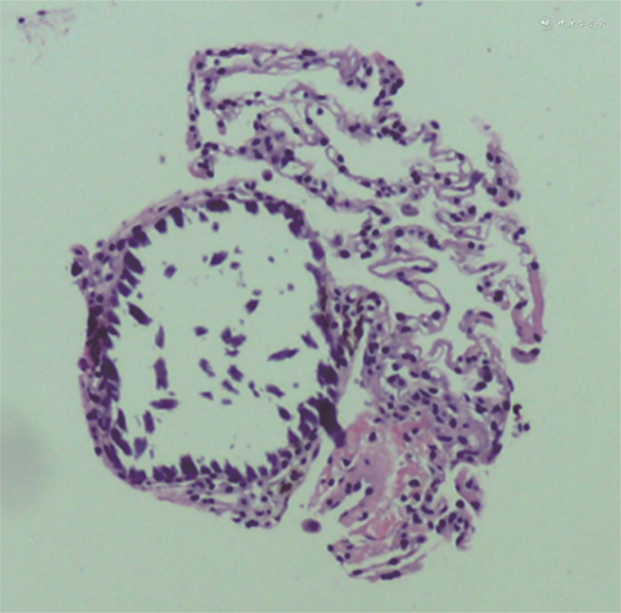

辅助检查:血常规,动脉血气分析,肝、肾功能均未见异常,结核分枝杆菌特异性细胞免疫反应检测、结核菌素试验、痰培养、痰涂片抗酸染色、肺泡灌洗液培养、肺泡灌洗液抗酸染色、血清结核抗体均为阴性,涎液化糖链抗原6 211 kU/L(参考值<500 kU/L),烟曲霉IgM抗体256.97 kAU/L(参考值 0~79.99 kAU/L)。胸X线片检查提示肺部间质性病变(图1A)。肺功能检查提示轻度阻塞性通气功能障碍,心脏超声未见异常,胸腹部增强磁共振成像见明显异常,胸部增强CT提示两肺弥漫间质病变,两侧胸膜钙化(图1B)。术后病理示肺泡腔内见多发破碎钙化结节,部分呈同心圆样改变,符合肺泡微石症表现(图2)。

PAM是以钙磷代谢紊乱,肺部微结石逐渐沉积为特征的一种罕见疾病[1]。近年来研究证实,PAM是由于SLC34A2基因变异导致的一种常染色体隐性遗传病,该基因定位于4p15.1-p15.3[2, 3]。国内报道大多为成人病例,儿童病例较少见。PAM是一种慢性进展的肺部间质性病变,大多于成年期发病,具有家族聚集性发病倾向,男性发病率高于女性[2,4]。PAM是由于编码Na+依赖的Pi转运蛋白的SLC34A2基因发生变异致病,影响肺泡液中无机磷的吸收,引起肺泡内无机磷的积累,从而导致磷酸钙在肺内的沉积[3]。SLC34A2的变异类型超过15种。PAM多发生于亚洲与欧洲地区,中国PAM患者大多数为外显子8发生变异,有1例外显子6发生变异,特别是8号外显子C.910A>T的变异具有高度重复性,本例患儿存在外显子8及外显子4的复合杂合变异,其中外显子8的变异类型与之前的报道一致[4, 5]。本例患儿具有典型的PAM表型,进一步丰富了SLC34A2的基因型。PAM的诊断主要通过影像学或病理学检查[2,4, 5, 6]。影像学检查结果会随着疾病进展逐渐加重,疾病早期可表现为散在微小钙化结节,结节会逐渐增大增多,主要集中在中下肺野,疾病较重时,可以出现“白描征”“暴风雪征”“沙暴征”或“火焰征”,具有确诊意义。PAM典型的病理改变是肺泡腔内不规则分布的同心圆样层状结石。镜下可见结石沿支气管、血管分布,大多位于肺泡腔内,也可见于肺泡壁,并向肺泡腔内突入。部分患儿的肺泡灌洗液或痰液中可检出微结石,对诊断也有帮助[2]。PAM部分患儿症状轻微或无明显症状,随着年龄进展,可出现气促、胸闷、喘息、乏力劳力性呼吸困难等症状[2]。PAM的症状与年龄相关,在儿童期症状多不典型,本例患儿无明显临床症状,胸部影像学存在间质性改变,胸膜钙化等特点,肺组织病理学可见同心圆样钙化结节,在基因诊断前已经可以临床确诊[1]。但由于儿童PAM比较罕见,对于患儿胸部影像学的“白描征”认识不足,故诊断需依赖病理学或基因检查相关结果。PAM尚没有有效的治疗手段[2, 3, 4]。应用羟乙磷酸钠治疗PAM的报道,但其疗效尚不能肯定。肺移植是终末期PAM患者的有效治疗手段,国内外均有移植成功的报道,移植后的远期疗效仍需要进一步观察研究[6]。SLC34A2基因相关性PAM在儿童中是一种罕见的肺部间质性疾病,进展缓慢,部分患儿无明显临床表现或仅有轻微咳嗽症状。对于肺部弥漫性间质性改变,广泛异常钙化的患儿,应考虑到PAM的可能,建议可完善肺泡灌洗术、肺活检等相关检查明确病因。根据患儿的典型的影像学表现,病理结果或基因检测结果可以明确诊断。